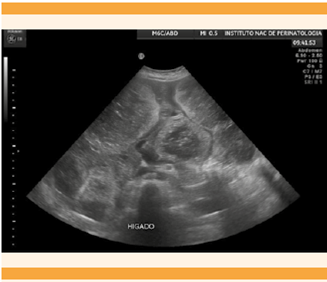

El ultrasonido hepático reportó al parénquima heterogéneo y con múltiples imágenes ovaladas, de bordes regulares, debidamente definidos, de predominio ecogénico, que alternan con áreas de mayor ecogenicidad, la mayor incluso de 10 x 7 x 8 x 6 cm en relación con probables hemangiomas.Figura 1

Figura 1 Ultrasonido hepático; corte medio sagital con imágenes sugerentes de hemangiomas hepáticos gigantes.